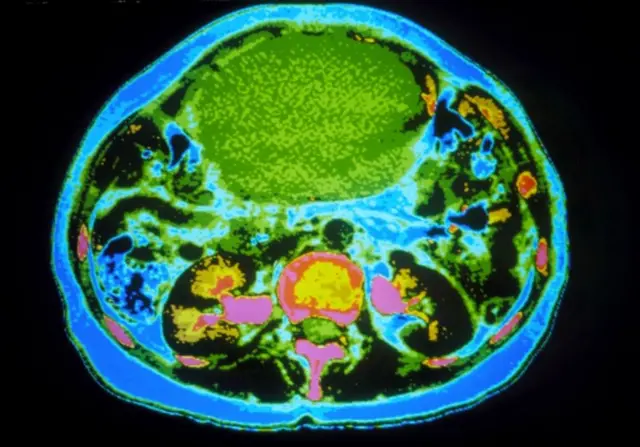

منبع تصویر، SPL